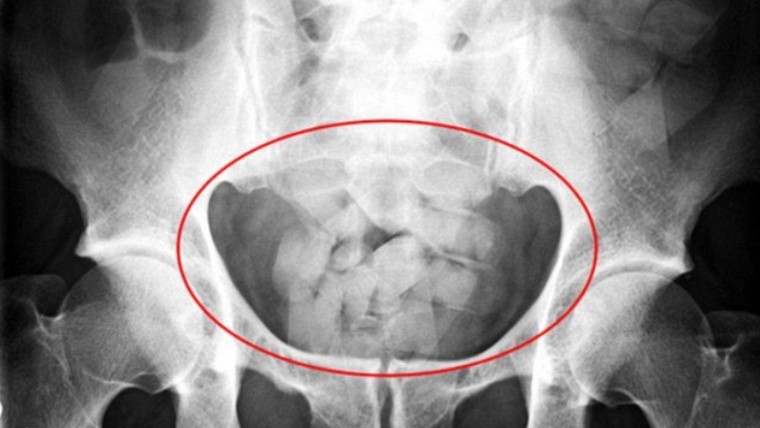

Las cápsulas se detectan a través de tomografías computadas.Las cápsulas se detectan a través de tomografías computadas. (archivo TN)El juez federal de Reconquista Aldo Alurralde alertó por el creciente uso de "mulas" en el norte provincial. Precisó que generalmente se contratan a mujeres, quienes deben ingerir cápsulas de cocaína y llegar al destino señalado. También explicó cómo varía la manera de ingresar droga a distintas localidades.

Entrevistado por los periodistas Roberto Caferra y Evelin Machain (Radiópolis, Radio 2), el magistrado expresó su "preocupación" por el aumento de casos de "capsuleros o mulas" en la región. "Las organizaciones suelen elegir a las mujeres para la ingesta de las cápsulas porque tienen el tracto intestinal más lento. Por lo general, no comen nada durante el viaje y sólo toman algunas bebidas. Cabe remarcar el riesgo que corre su organismo en caso de que se rompa alguna de esas envolturas", comentó.

"Tuvimos el caso de una mujer. Tenía 81 cápsulas de cocaína en su cuerpo. Para tomar dimensión, cada una tiene cuatro centímetros de largo y uno de diámetro. Llevaba poco menos de un kilo", añadió.

Por último, señaló que cuando detienen a una "mula", a veces deben "esperar días" para tomarle declaración indagatoria, porque tardan en evacuar las cápsulas de cocaína.